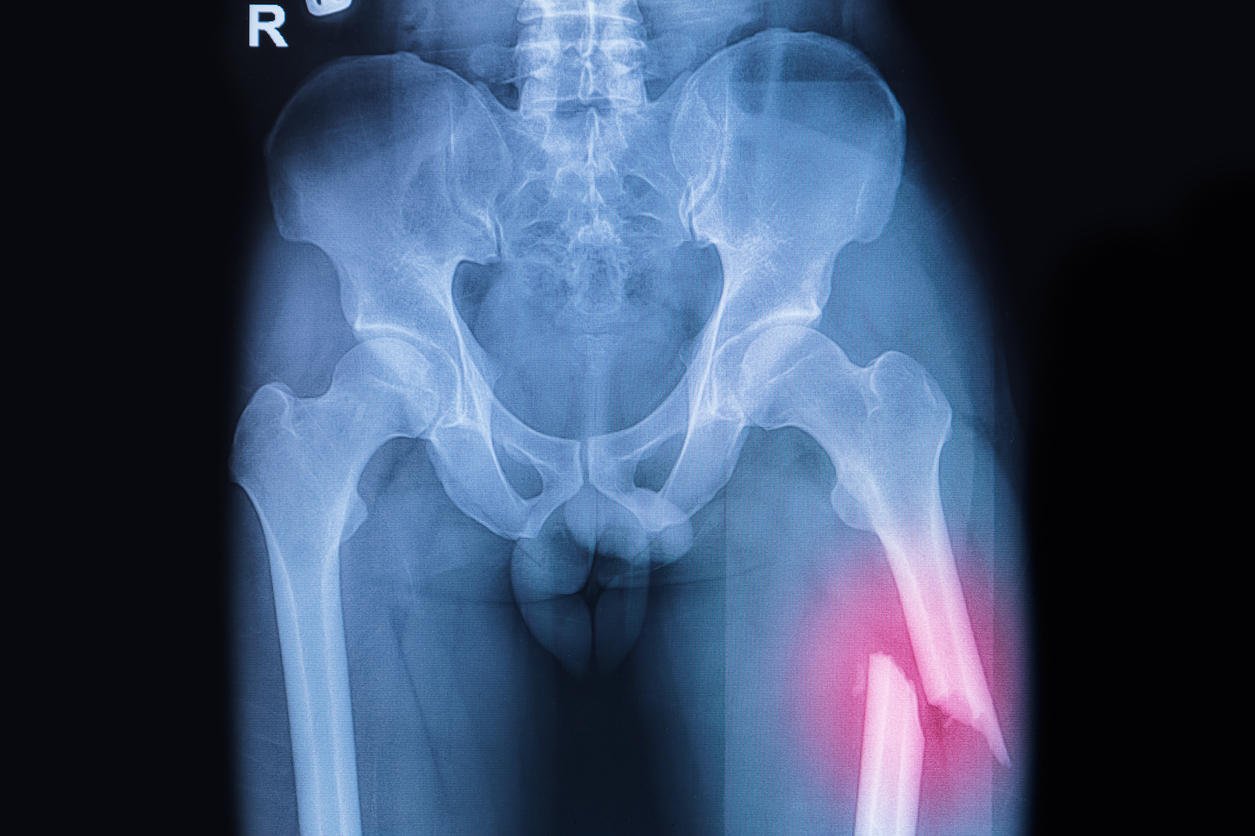

fémur fracturé, radiographie de la cuisse cassée image

La fracture du fémur d’une personne âgée est fréquente suite à une chute. L’opération du col du fémur est, dans ce cas, systématiquement nécessaire pour pouvoir guérir. En revanche, en cas de fracture de la diaphyse fémorale (c’est-à-dire de la partie centrale de l’os), il est rare qu’une opération soit pratiquée. De fait, les temps de récupération et de consolidation diffèrent d’un cas à l’autre.

En cas de fracture de la diaphyse fémorale (généralement suite à un choc particulièrement violent), la pose d’une prothèse n’est pas le traitement le plus indiqué. Cette fracture peut, par exemple, concerner des enfants et, dans ce cas, la pose d’un plâtre sera préconisée. Chez les adultes, l’opération consiste à placer un clou centro-médullaire ou parfois des fixateurs externes, notamment en cas de fractures déplacées. Plus le traitement et l’immobilisation du membre inférieur sont précoces, plus le risque de complication est faible et le temps de consolidation réduit. En cas de fracture de l’extrémité supérieure de la diaphyse chez une personne encore jeune et/ou aux os solides, le temps de consolidation est de 4 à 6 semaines la marche avec des béquilles étant nécessaire dans les premiers temps.